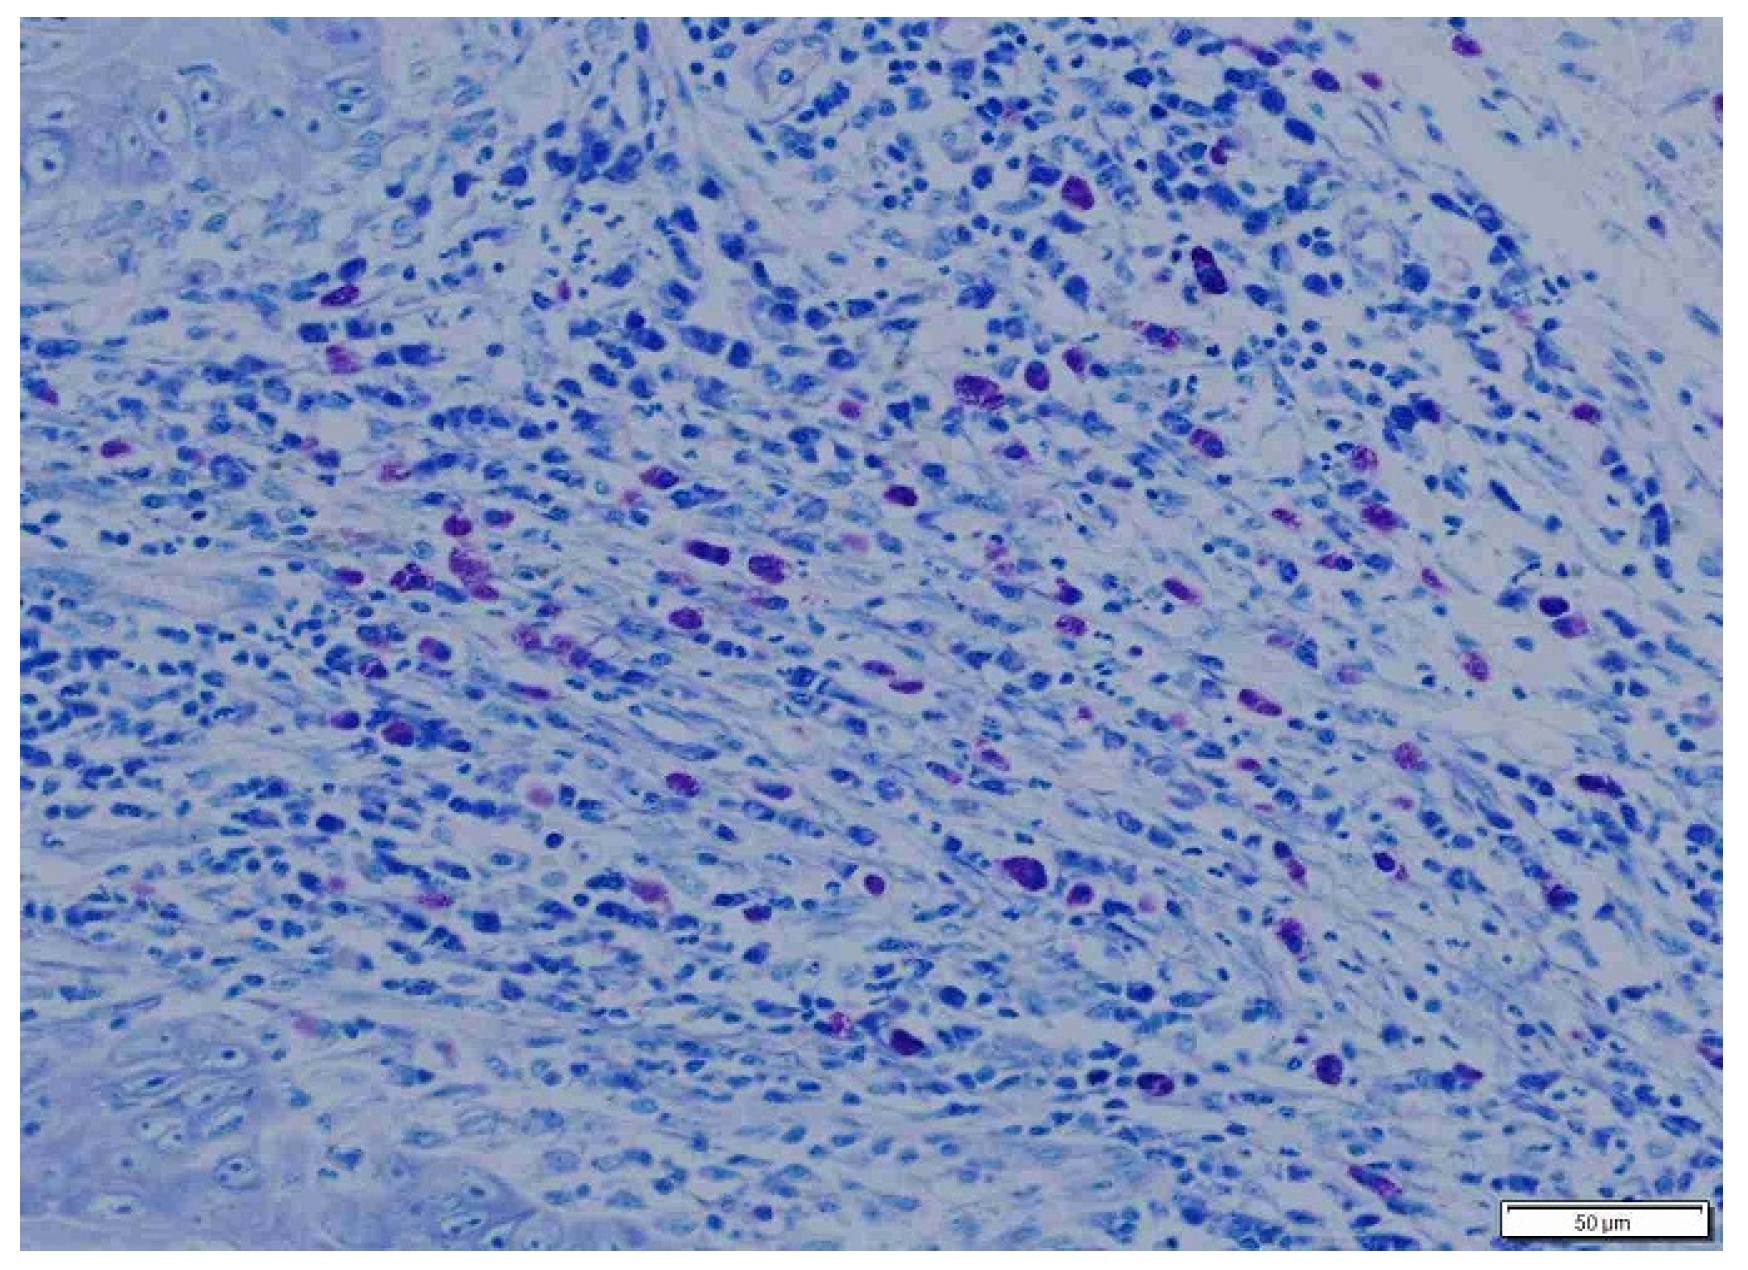

2.4. Histopathology

3. Results

| Total PTMC | 136.53 ± 59.34 a3 | 202.96 ± 110.21 b3 |

| Total ITMC | 75.3 ± 18.06 a6 | 200.1 ± 106.27 b6 |

| Total MC | 211.83 ± 46.15 a7 | 403.01 ± 107.34 b7 |